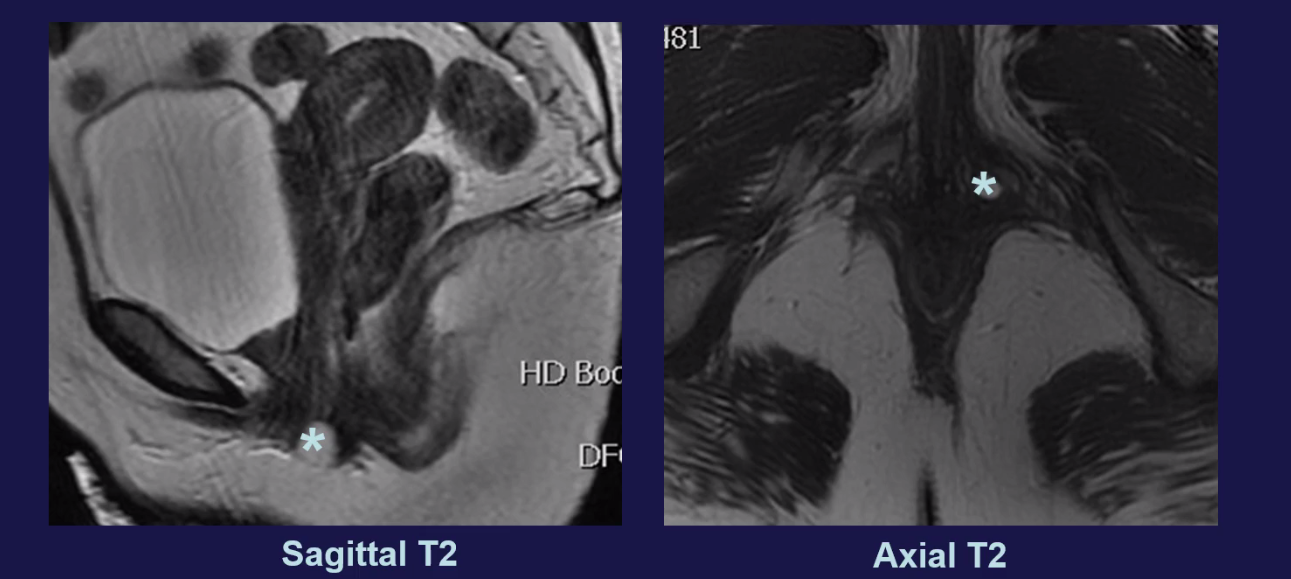

• kyste Para-urétral

• Très inférieur

uretre urètre urethre urèthre gland glande skenne skene skhene shkene skhenne glande